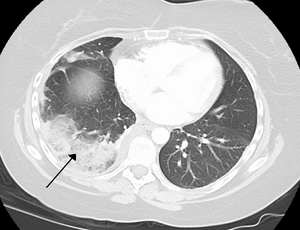

تصوير مقطعي محوسب للصدر (نافذة الرئة المحورية).